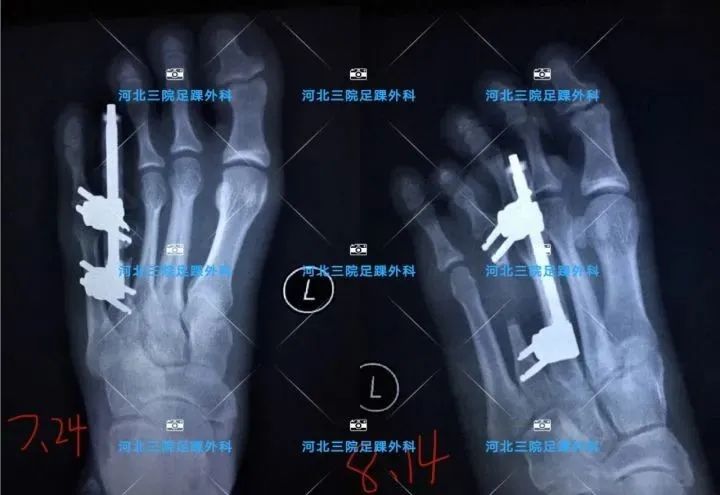

从X线片可以看出,第四跖骨先天短缩(蓝线标注处),进而表现为第四趾短小。

通常采用手术治疗,手术的目的是将短缩的跖骨延长,从而达到第四趾恢复到正常的长度。采用了伊利扎若夫技术,原理为牵张成骨,就是将骨质切开,保留软组织和血供,采用特制的牵引装置固定两端,应用张应力法则逐步施加拉力将骨段缓慢牵拉,不断刺激机体组织,激发人体组织再生潜能,使截骨间隙形成新骨,达到骨再生的目的。手术后一周开始延长,1日4次,每次0.25mm平移,每日延长1mm。达到满意的长度后,保持外固定架继续固定1个月。

手术将短缩的跖骨“锯”断,然后用外固定延长架固定。

绿色的就是微型延长用外固定架,手术在局麻下进行,只需要切1cm的小口,术后几乎不会留疤。

随访X线片,可见跖骨已经延长,中间延长的骨部分已形成骨痂,但是X线显影不明显